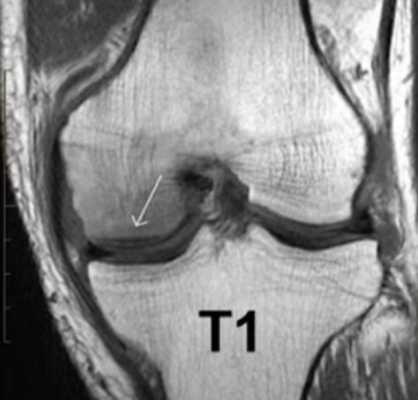

МР-скан коленного сустава в Т1 режиме (стрелкой указан костный отек)

В структуру сочленения входит множество мелких элементов. Правильно прочитать томограммы сможет специалист в области рентгенологии с внушительным практическим опытом. В спорных ситуациях результаты МРТ предоставляют для чтения нескольким врачам. Человек без медицинского образования и соответствующих навыков не сможет расшифровать снимки. Чтобы понять заключение рентгенолога, требуются глубокие знания. По этой причине трактовку результатов МР-томографии лучше доверить врачу (травматологу или ортопеду).

При МРТ получают серии монохромных снимков анатомической области в аксиальной, сагиттальной и фронтальной плоскостях. При изучении изображений врач видит контуры различных элементов сочленения. Расшифровка МРТ-снимка коленного сустава подразумевает оценку сканов в сравнении с нормой. МР-томограммы называют срезами, поскольку изображения производят послойно, с шагом 1-2 мм. Врач последовательно изучает анатомическую зону на предмет соответствия всех структур норме. В процессе расшифровки фото обращают внимание на качество визуализации элементов, четкость контуров, присутствие зон измененного МР-сигнала (гипер- или гипоинтенсивного) в различных режимах сканирования (Т1 ВИ, Т2 ВИ, ДВИ, подавление жира).